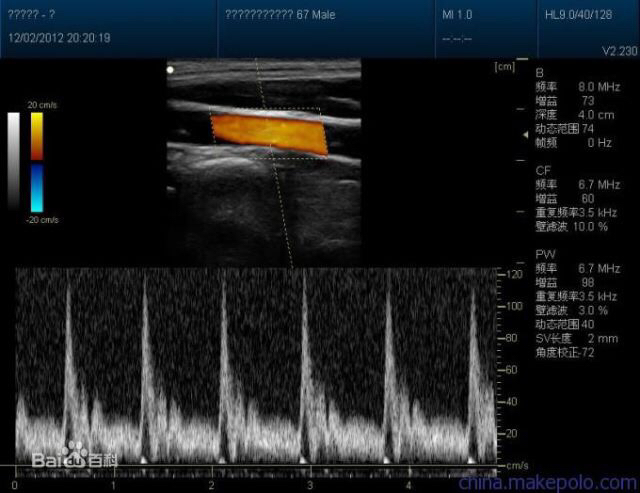

如果你们曾经到神经内科就诊过,比如说你有头疼、头晕,出现了手脚麻木,医生可能会给你做一个脑血管筛查,叫做经颅多普勒超声。

通常情况下,稍微好一点的体检套餐里面往往都会有经颅多普勒超声。对多数人群来说,经颅多普勒超声主要检查颅内血管是否存在动脉紧张度增高,有无弹性减退,有无早期的动脉硬化,有无颅内动脉狭窄。

经颅多普勒超声用于检测颅内血管的情况,颈动脉超声用于检测颈部(颅外)血管的情况。

为什么要重视颈动脉超声,因为颈动脉离体表最近,都能摸到或者看到,所以超声检查最方便最准确,做这个检查最主要的目的是检测有没有动脉硬化斑块。

对于有不良生活嗜好的人,如果到了一定岁数,一般来说我们建议去查一下颈动脉超声。不良嗜好是什么?吸烟、饮酒、吃肥腻的东西,在外面就餐,久坐少动。如果有不良生活习惯,同时又出现了肥胖、高血压、高血脂、糖尿病,那么心脑血管病危险会大幅升高。

如果经颅多普勒超声或者颈动脉超声提示患者可能有颅内或者颅外动脉狭窄,那就需要做下一个检查,就是血管成像。